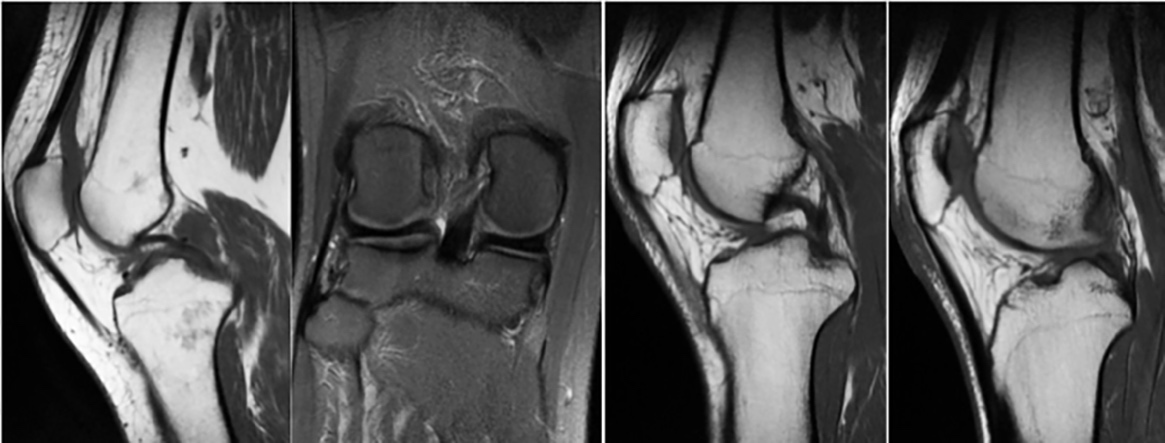

Los LMF se originan en el cuerno posterior del menisco externo y se insertan en el cóndilo femoral interno por delante (ligamento de Humphrey) y por detrás (ligamento de Wrisberg) del ligamento cruzado posterior (LCP) (Figura 7) (Figura 8).

El LMFp es visible y está separado del LCP, es pequeño de forma ovoide con señal poco intensa, inmediatamente por detrás del LCP y el anterior aparece como un bulto discreto de baja señal a lo largo de la superficie cóncava del LCP o como una pequeña formación ovoide de baja señal justo por delante del LCP. Cuando son visibles en RM, el LMF anterior (LMFa) y el posterior tienen una inclinación diferente debido al distinto punto de inserción en el cóndilo femoral lateral; la oblicuidad del LMF posterior es más acentuada que el anterior [27]Para Kaplan et al., [28] el LMFa se origina del LMFp, como si fuera su rama anterior; Gupte et al., [13] los consideran estructuras independientes que coexisten en el 50% de las rodillas, con orígenes e inserciones individualizados. Lahlaidi y Vaclavek [5] proponen una explicación embriológica para comprender las variaciones anatómicas observadas, sugiriendo que el sitio del LCP durante el desarrollo embriológico determina la presencia y posición de los LMF.

Figura 7. A, b) Cuerno posterior menisco externo y LMFp

Los dos LMF conectan el cuerno posterior del menisco lateral a la cara interna del cóndilo interno del fémur como estructuras independientes con diferentes inserciones meniscales y femorales [13][14][16][29]. El LMFa pasa por delante del LCP y se inserta distal muy cerca del límite de la superficie del cartílago articular y una porción de sus fibras se entremezclan con las fibras del LCP en su inserción femoral [22]; el LMFp transcurre por detrás del LCP y se inserta más proximal, cerca del techo de la escotadura intercondílea y sus fibras no se mezclan con las fibras del LCP.

Figura 8. A, b, c) Cuerno posterior menisco externo. LMFa